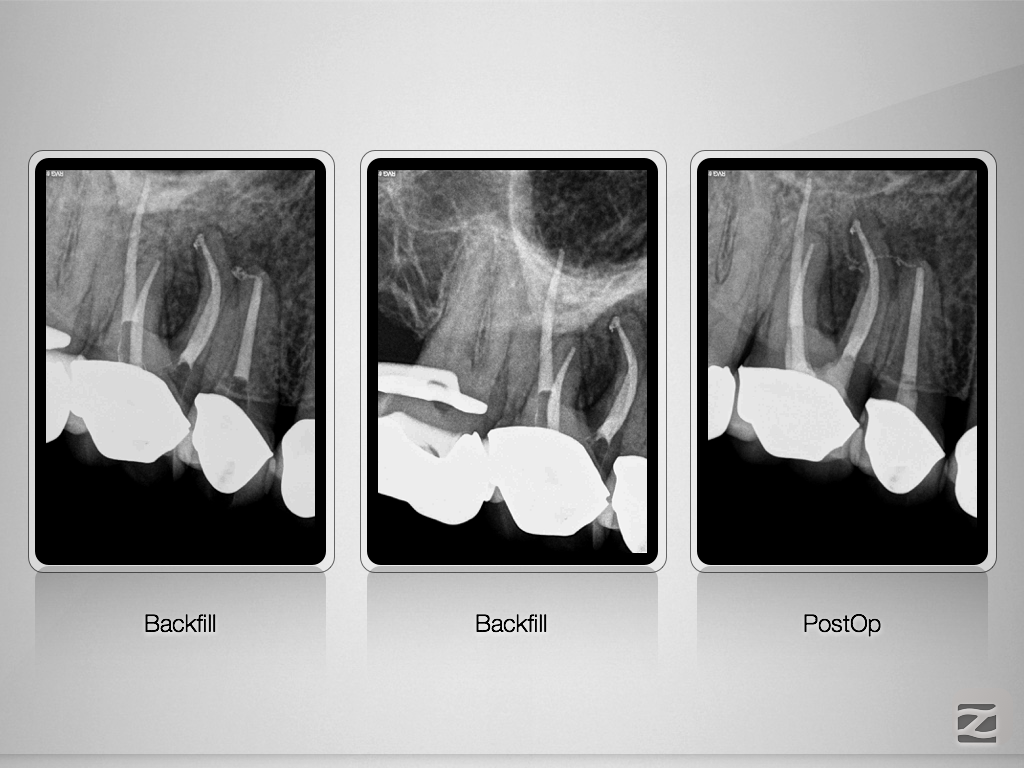

Endo-Paro-Läsion